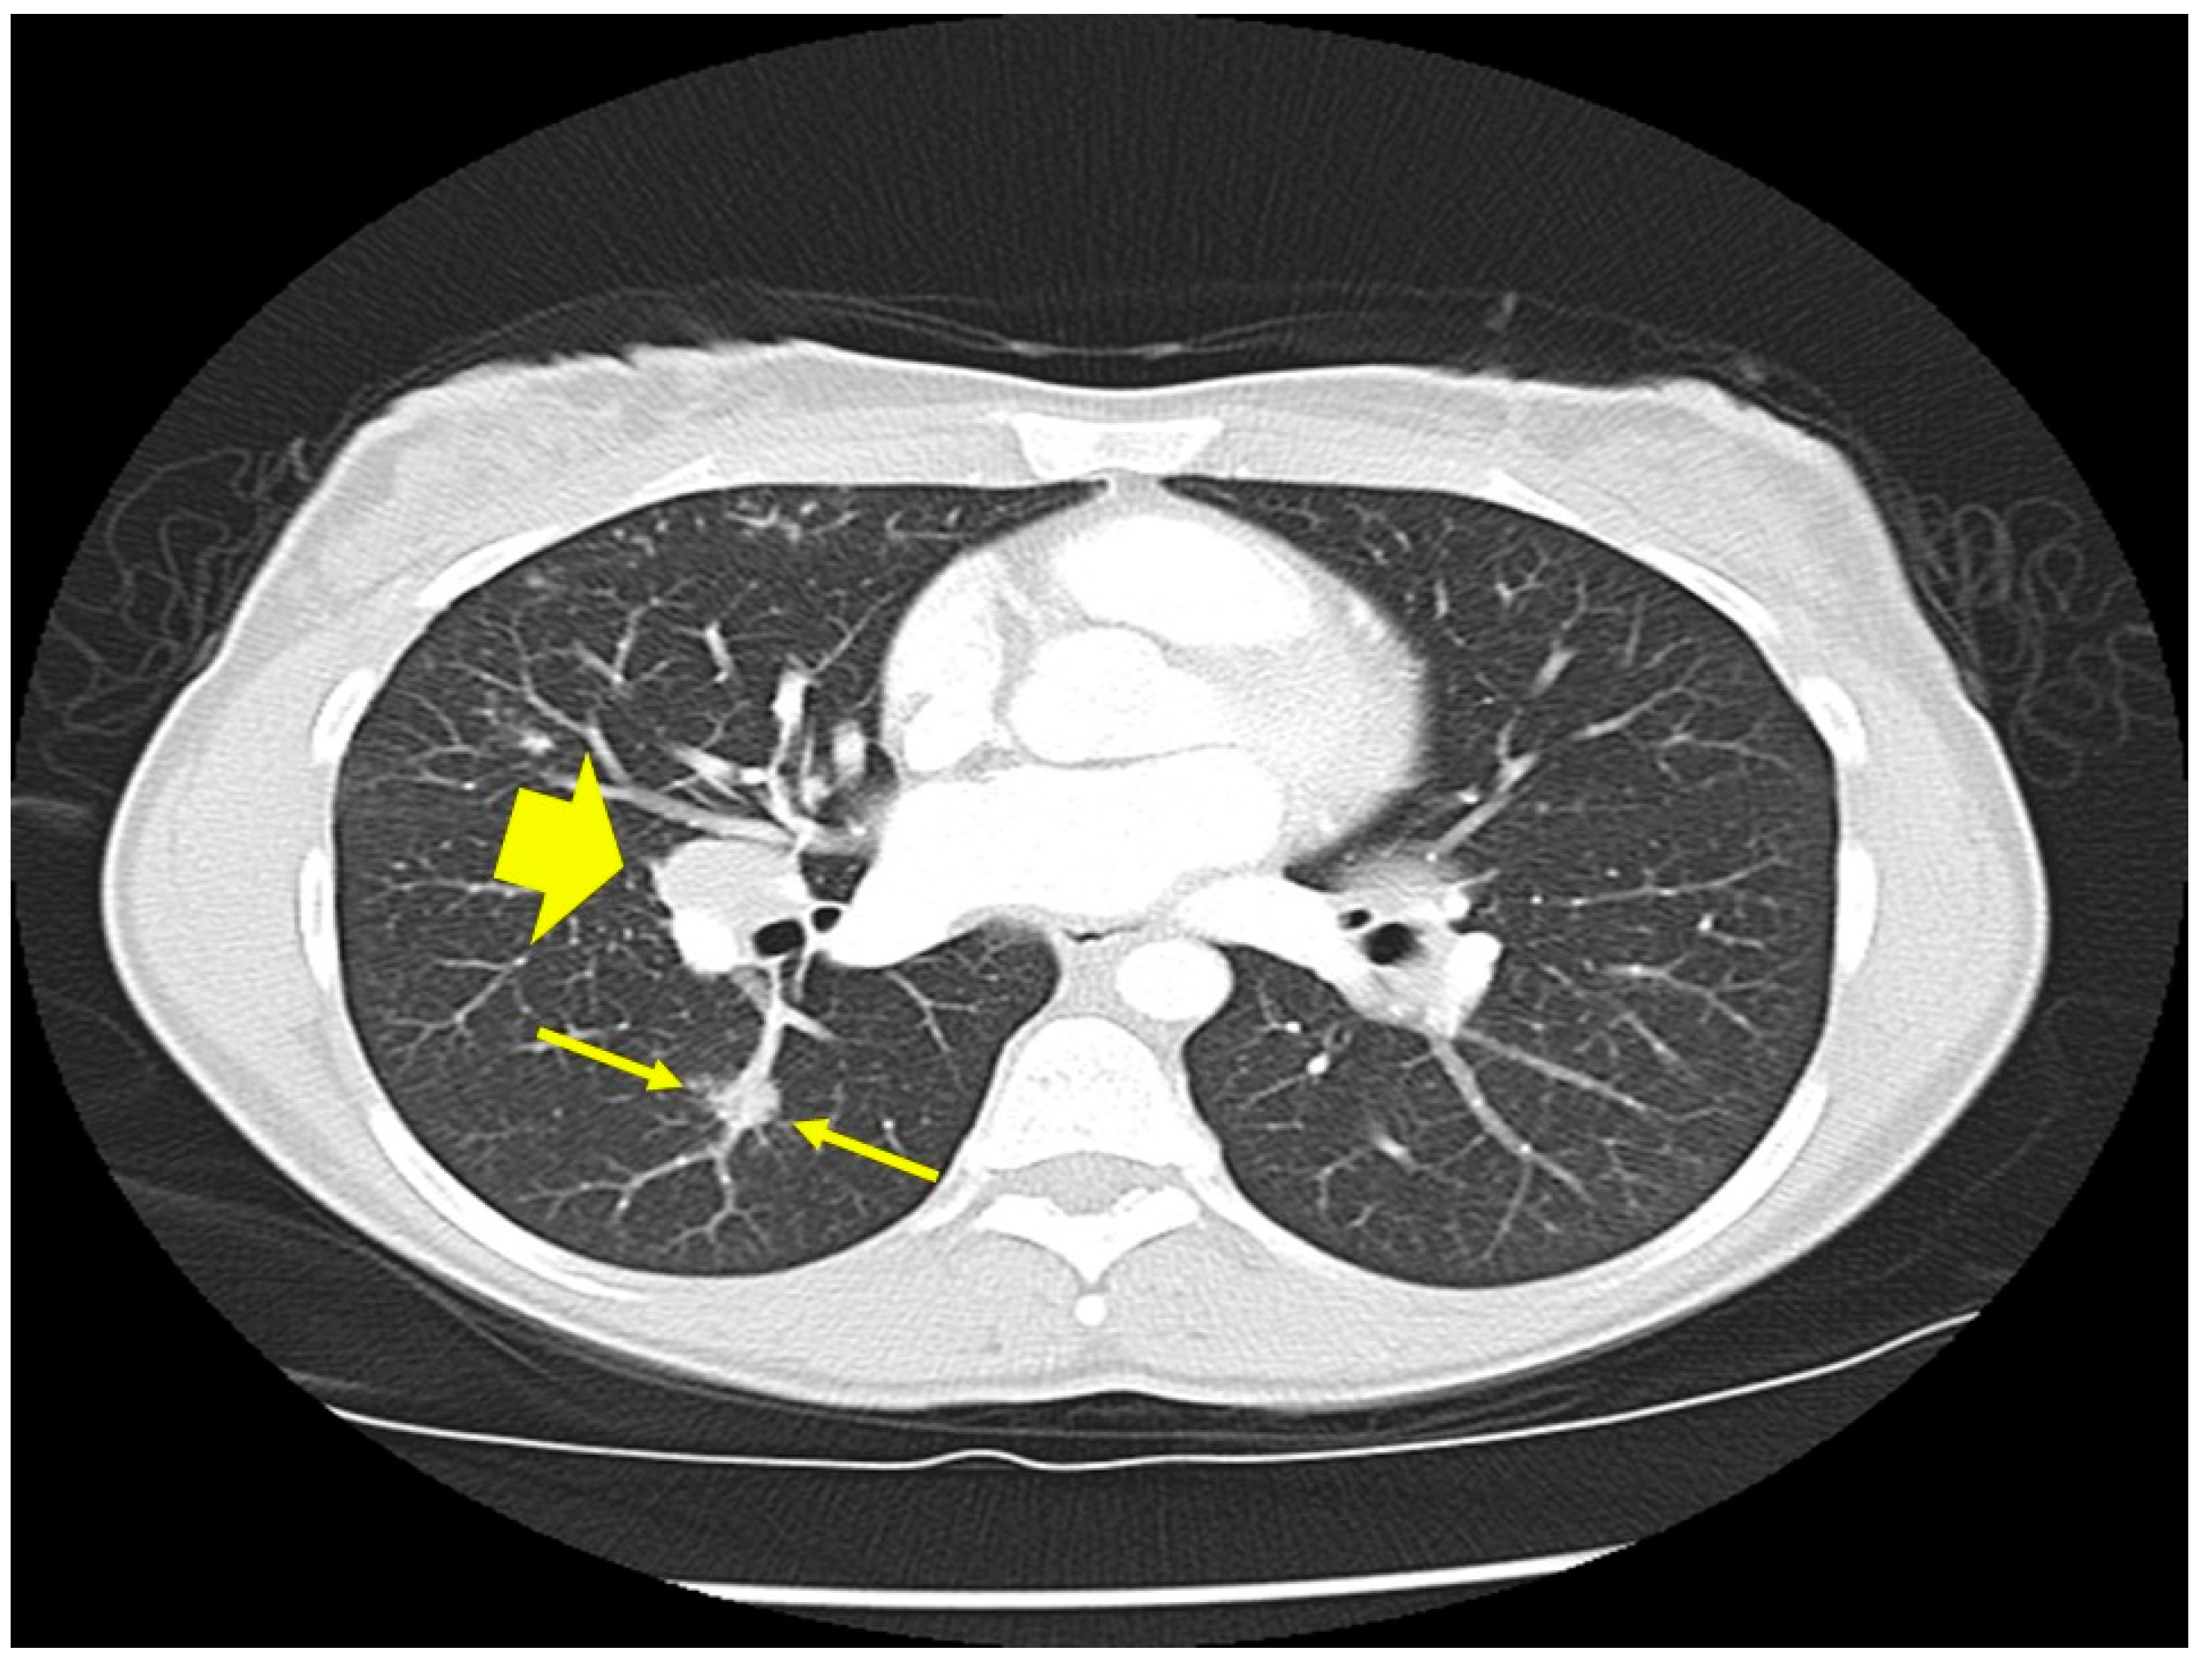

Figure 3.

Chest CT scan image of a patient with pulmonary sarcoidosis demonstrating lung opacities from granulomatous inflammation around pulmonary vessels (thin arrows). Scatter parenchymal nodules and hilar adenopathy are seen, especially on the right (thick arrow).